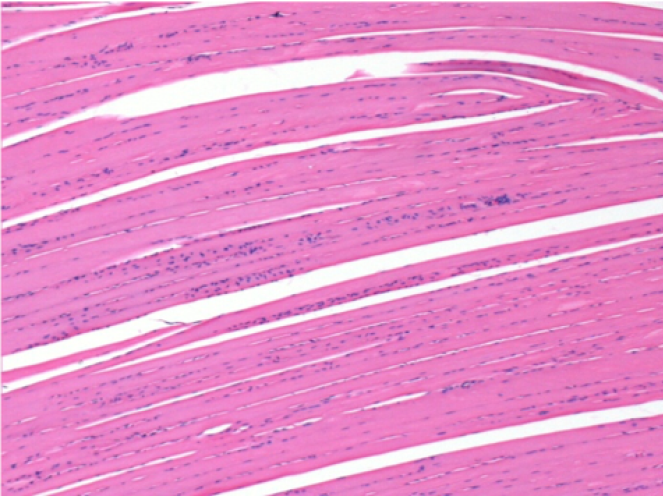

1 mese dopo Iniezione Endopeel

Scatola Nr 3

1 mese dopo Iniezione 0.1ml di Endopeel nel muscolo pretibiale destro ( Dx) .

Che cosa viene visualizzato in nero nella figura Sx : 100x-Giorno30 non é una necrosi come potrebbe immaginare un dilettante.

In effetti, 4 conclusioni devono essere prese in considerazione

- un artefatto di colorazione

- un`assenza di necrosi

- un`apoptosi

- un processo biorigenerativo

Sx : Controllo-100x-Giorno30

Dx:100x-Giorno30

Dx :400x-Giorno30